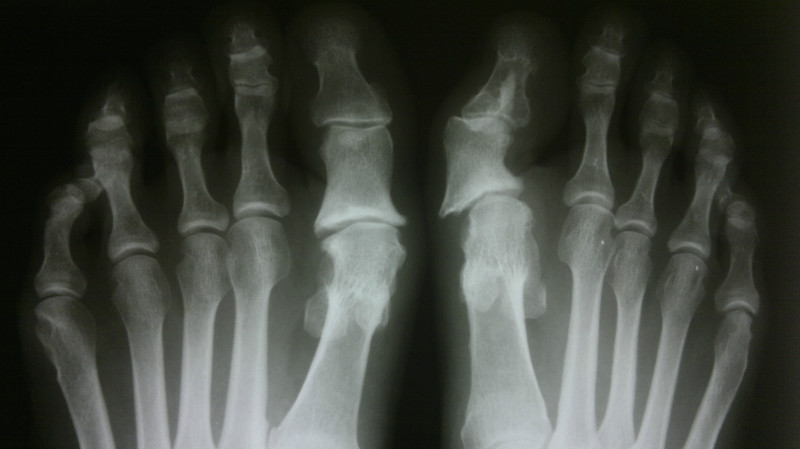

С Наступающим Новым Годом! Обратилась пациентка 42лет, 4 года назад оперирована в Боткинской. Левая стопа не беспокоит, в правой  при ходьбе боли в 1 плюснефаланговом суставе, неудобство при ношении обуви, "косметика смущает"..При осмотре: подвывих 1 пальца, вправляется, нестабильный. Что можно предложить? Релиз из латерального доступа и попробовать укрепить капсулу с медиального доступа  имитируя коллатеральную связку, основную фалангу временно зафиксировать в вправленном положении спицей недельки на 3-4? Спасибо!                                                                                                          PS:  В Боткинскую не хочет, доктор говорит была пожилая, сказала "не знаю чем помочь". Присылаю картинки...